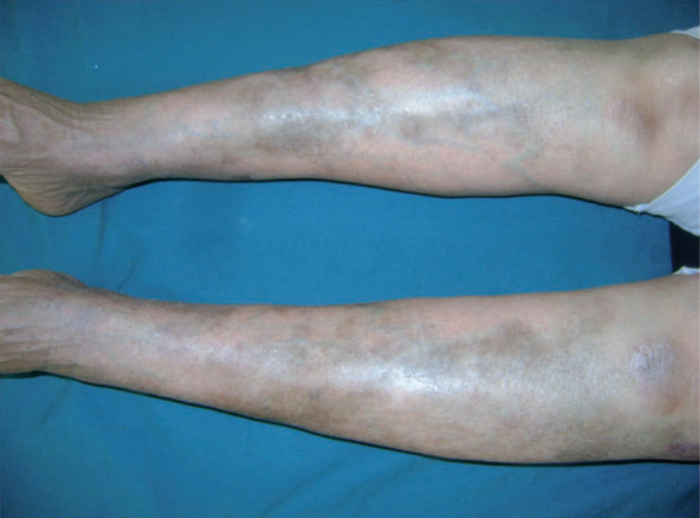

羟氯喹是系统性红斑狼疮的治疗过程中最常用的抗疟药物,但此药却与黑色素的亲和性很高,容易导致黑色素在皮肤中沉积。

研究表明,25%的狼疮患友使用羟氯喹后会出现皮肤色素沉积的不良反应,并且这种黑色素沉积大部分集中在腿部,同时也可在脸部、背部皮肤黏膜等部位出现。这一表现同时也警示患者可能出现了眼毒性,需及时去医院进行眼底检查以明确诱因。[3-4]